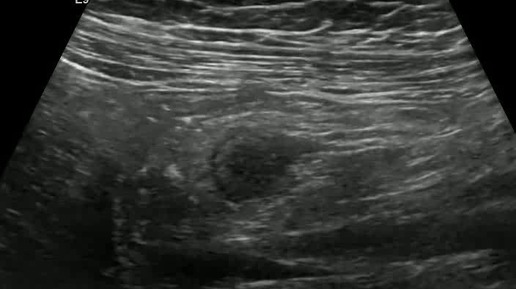

Ультразвуковые находки от врача УЗД Зорина Я.П.